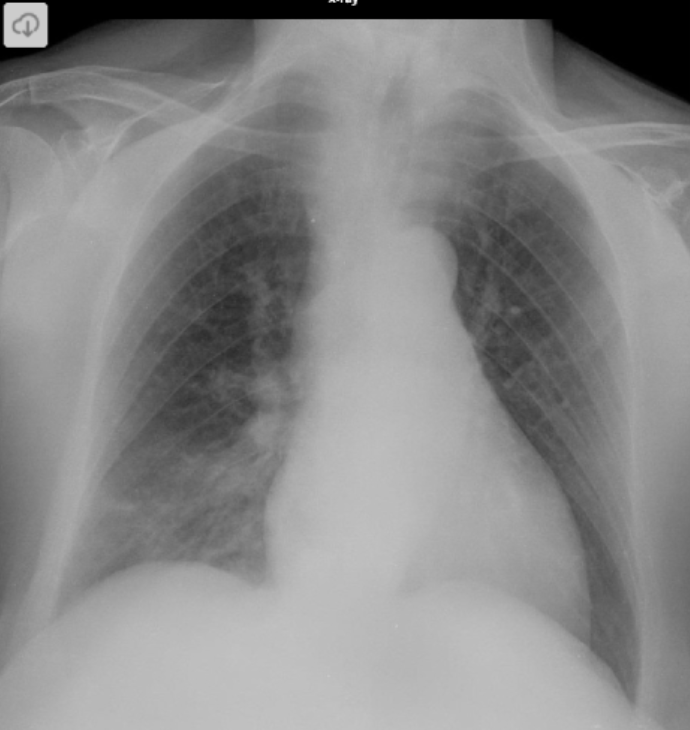

Opacidad en vidrio deslustrado en el lóbulo inferior derecho.

3 días después

Aumento leve de la opacidad en vidrio deslustrado, sin cambios en los otros lóbulos.

aunque la infección por SARS-CoV-2 (COVID-19) se describe por tener un curso rápidamente progresivo, a veces puede manifestarse como vidrio deslustrado que permanece relativamente estable. En este caso, la paciente, a pesar de su edad, permaneció clínicamente estable y fue dada de alta a la cuarentena domiciliaria.